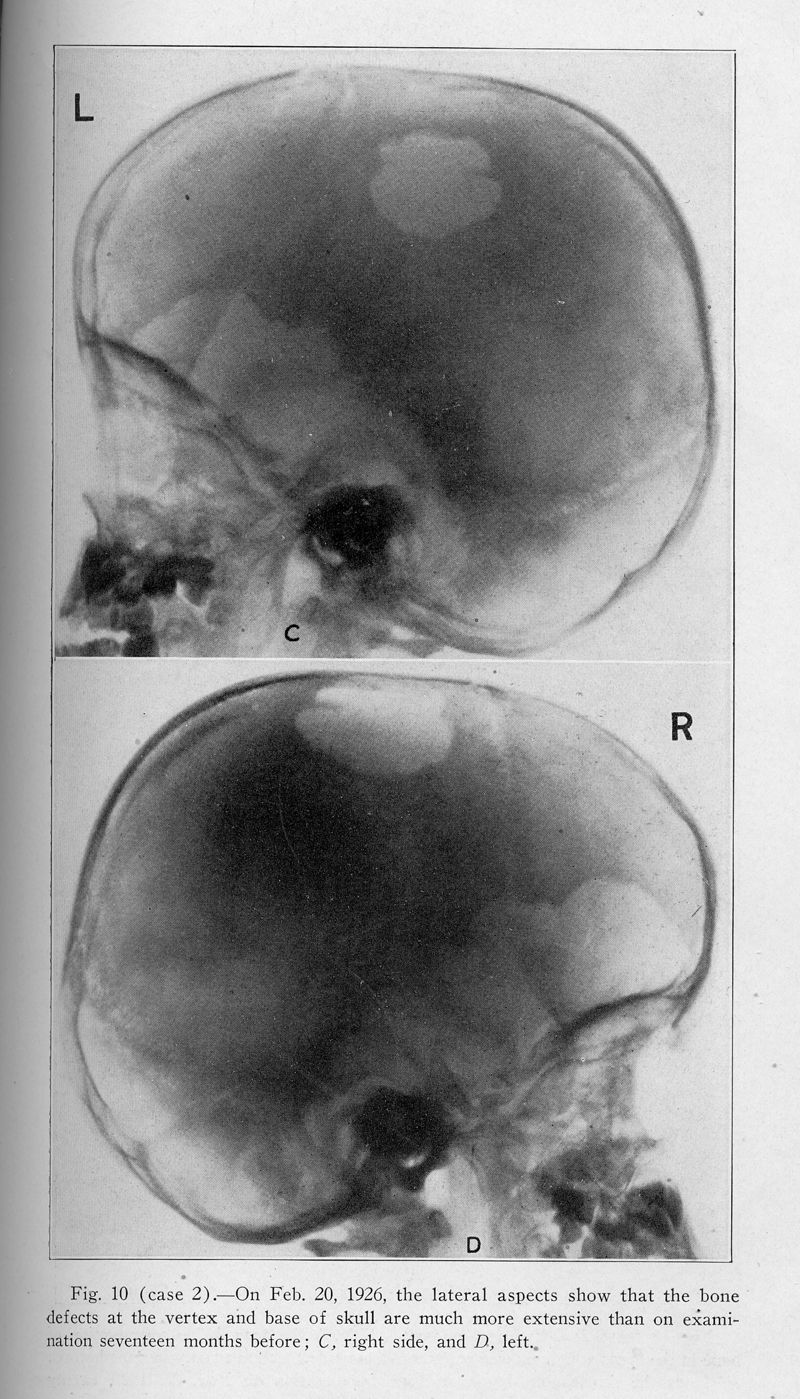

Xanthomatosis and the reticuloendothelial system. Correlation of an unidentified group of cases described as defects in membranous bones, exophthalmos and diabetes insipidus (Christian's syndrome)

In : Archives of internal medicine (1908), 1928, Vol. 42, pp. 611-74